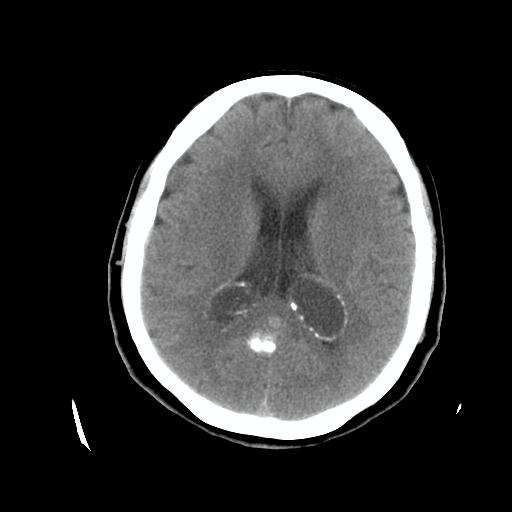

标题: CT24768:双侧脑室内囊性病变,主各位站友会诊。 [打印本页]

标题: CT24768:双侧脑室内囊性病变,主各位站友会诊。

患者女,62岁,临床提供头痛、头晕数月,无恶心及呕吐,近日加重。请各位站友看看,能否定为双侧脑室脉络丛囊肿,如果不能,应考虑什么?谢谢!

支持脉络丛囊肿,建议mr检查

支持脉络丛囊肿,建议mr检查.

支持 双侧侧脑室脉络丛囊肿;建议行mr检查。